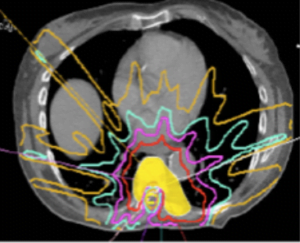

Oncological assessment is centred around the degree of response to potential treatment such as cEBRT, SRS, surgery, chemotherapy, hormonal, targeted or immunotherapeutic agents. Currently radiation is the mainstay of spinal metastasis and therefore the primary consideration. On the basis of expected response to cEBRT tumours may be considered radiosensitive (such as lymphoma, breast or prostate) or radio resistant (such as sarcoma, melanoma, lung (Oncological assessment is centred around the degree of response to potential treatment such as cEBRT, SRS, surgery, chemotherapy, hormonal, targeted or immunotherapeutic agents. Currently radiation is the mainstay of spinal metastasis and therefore the primary consideration. On the basis of expected response to cEBRT tumours may be considered radiosensitive (such as lymphoma, breast or prostate) or radio resistant (such as sarcoma, melanoma, lung (NSCLS) and renal cell). The game has changed with the advent of SRS for these tumours with durable local control in patients with oligometastatic tumours treated with 24Gy regardless of tumour histology. The efficacy of high dose SRS for local control has reduced the need for extensive surgical resections with resultant morbidity. The game has changed with the advent of SRS for these tumours with durable local control in patients with oligometastatic tumours treated with 24Gy regardless of tumour histology. The efficacy of high dose SRS for local control has reduced the need for extensive surgical resections with resultant morbidity.